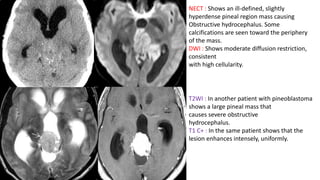

NECT : Shows an ill-defined, slightly

hyperdense pineal region mass causing

Obstructive hydrocephalus. Some

calcifications are seen toward the periphery

of the mass.

DWI : Shows moderate diffusion restriction,

consistent

with high cellularity.

T2WI : In another patient with pineoblastoma

shows a large pineal mass that

causes severe obstructive

hydrocephalus.

T1 C+ : In the same patient shows that the

lesion enhances intensely, uniformly.